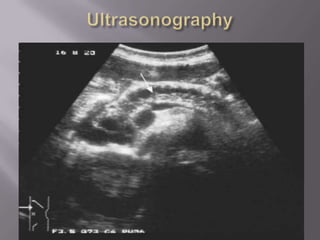

   Plain radiograph

   USG